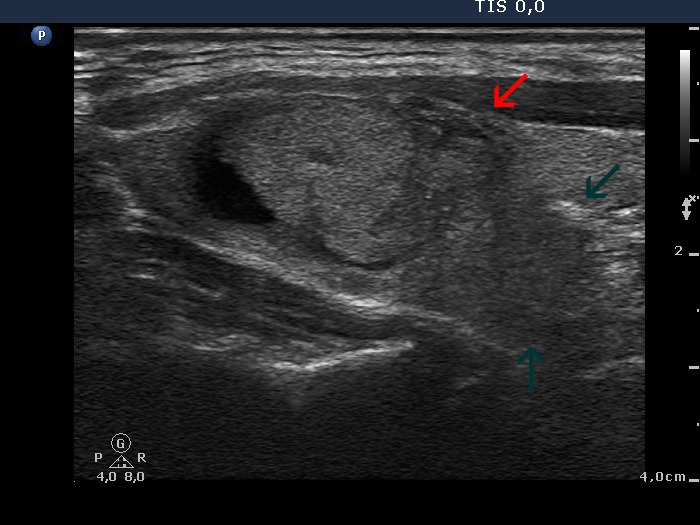

Thyroid cancers - case 678 (ultrasonographic picture 4)

Right lobe, longitudinal scan. Next to the cystic nodule (right in the image), there is a moderately hypoechogenic lesion with intranodular echogenic granules (red arrow). A similiar but less well circumscribed hypoechogenic area is found dorsal to the latter (green arrows).